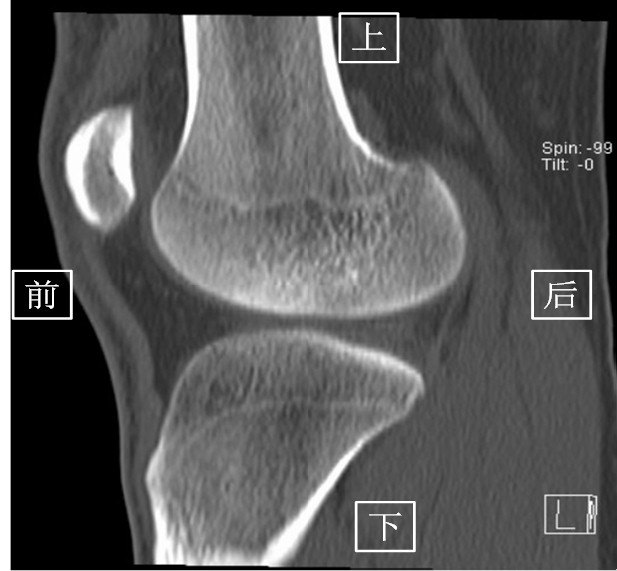

2.CT(以膝关节为例)

由于CT 是三维成像,包括矢状面,冠状面和横断面三个层面的扫描。一张CT片子也是包括医院、姓名、性别、年龄、检查日期、侧别、扫描序列等信息的。

矢状面---是从前向后、从内往外扫描成像。